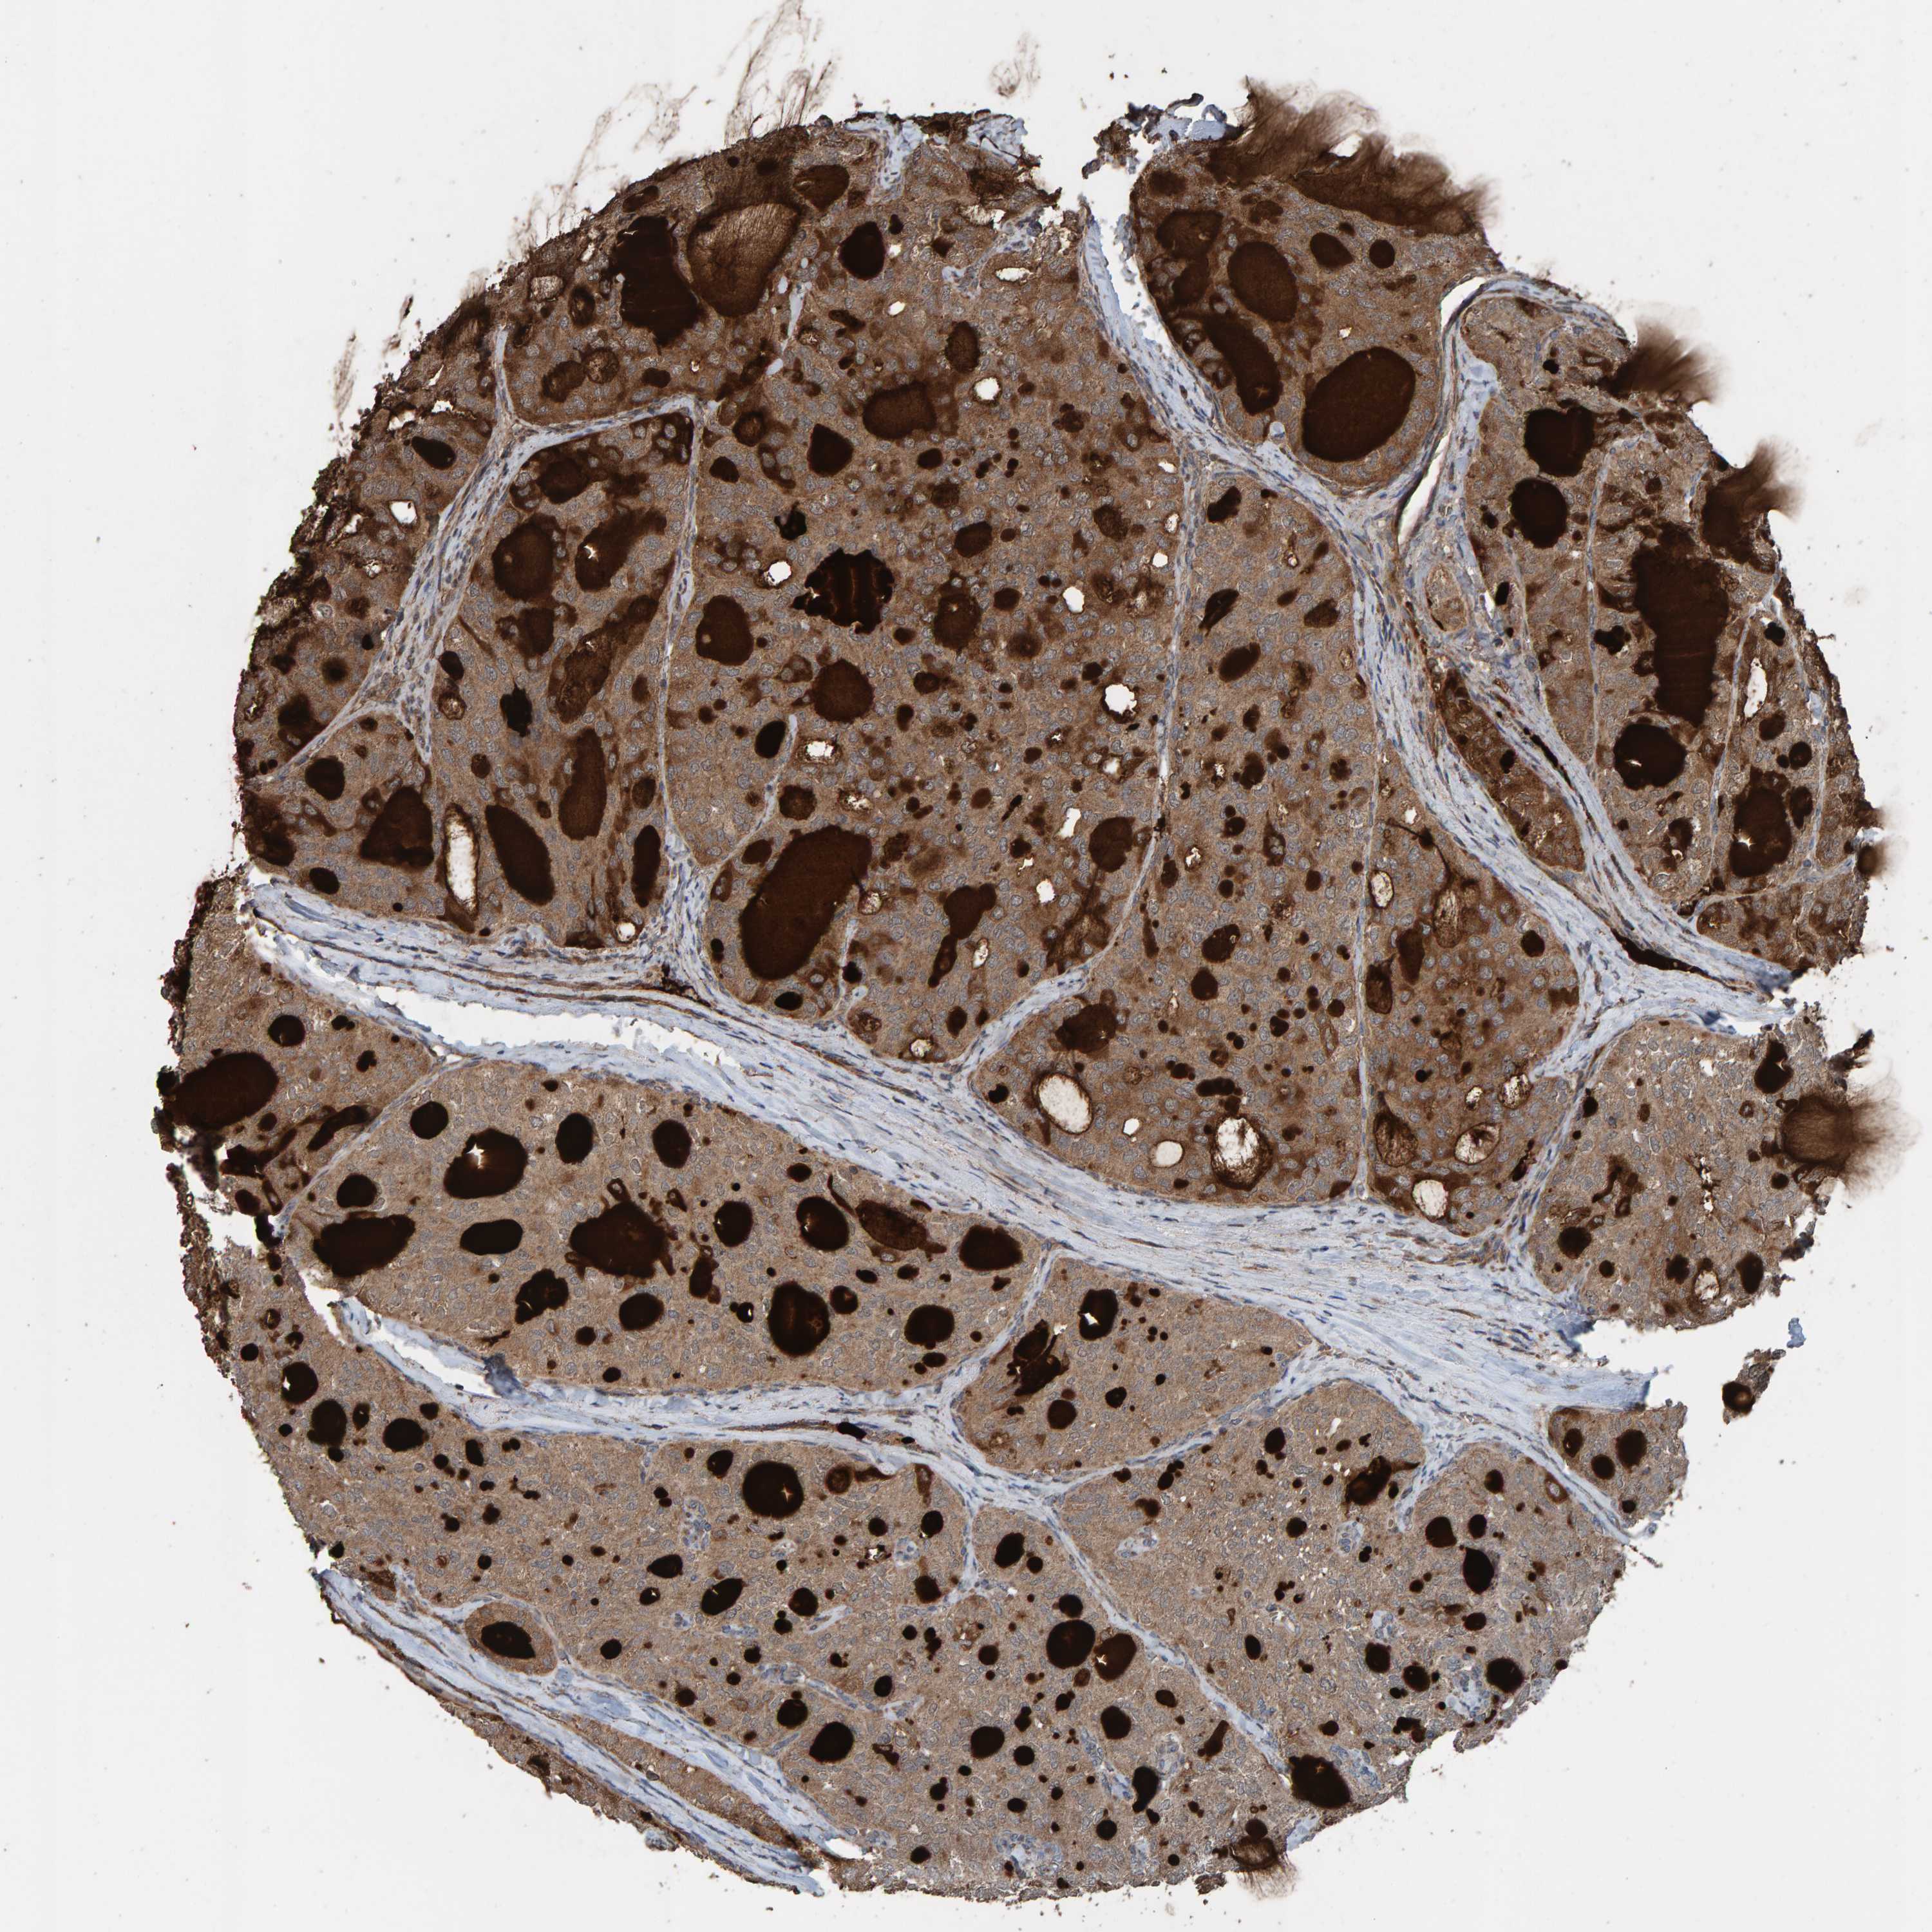

THYROID CANCER - Protein expressioni

A mouse-over function shows sample information and annotation data. Click on an image to view it in a full screen mode. Samples can be filtered based on level of antibody staining by selecting one or several of the following categories: high, medium, low and not detected. The assay and annotation is described here.

Note that samples used for immunohistochemistry by the Human Protein Atlas do not correspond to samples in the TCGA dataset.

Antibody stainingi

Antibody staining in the annotated cell types in the current human tissue is reported as not detected, low, medium, or high, based on conventional immunohistochemistry profiling in selected tissues. This score is based on the combination of the staining intensity and fraction of stained cells.

Each image is clickable and will lead to virtual microscopy that enables deeper exploration of all samples and also displays staining intensity scores, fraction scores and subcellular localization as well as patient and tissue information for each sample.

Antibody HPA023384

Staining

High

Medium

Low

Not detected

Intensity

Strong

Moderate

Weak

Negative

Quantity

>75%

75%-25%

<25%

None

Location

Nuclear

Cytoplasmic/membranous

Cytoplasmic/membranous,nuclear

Papillary adenocarcinoma, NOS

Follicular adenoma carcinoma, NOS